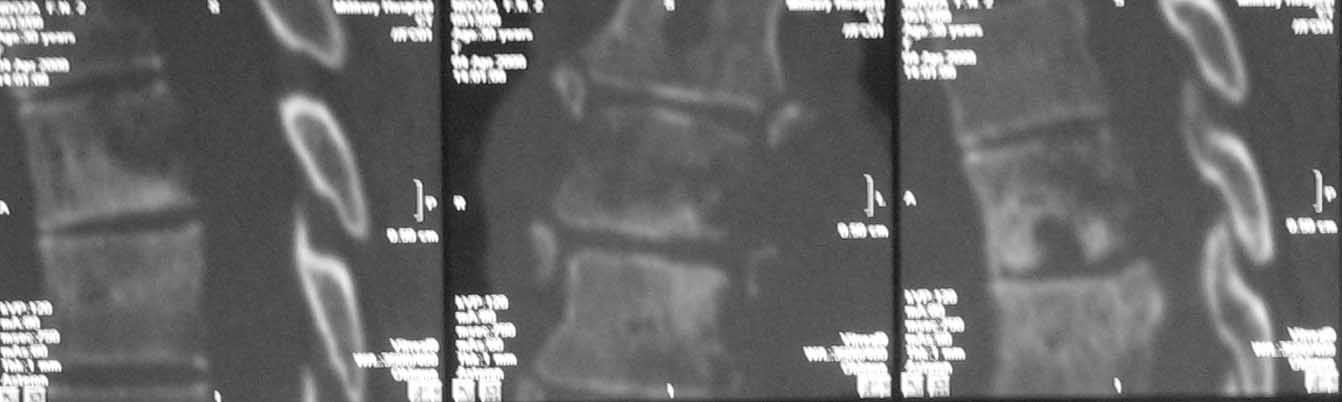

Дополнительное изображение 2. Наиболее поражены 5,6,7 и 9 грудные позвонки.

Доплнительное изображение 3. спинной мозг максимально компримирован на уровне 6 грудного позвонка.

Литические изменения в структуре тел позвонков особенно в нижнегрудном отделе при сохраненном дисковом пространстве наводит на мысль о спондилите с вторичным вовлечением дискового пространства( его исчезновение на уровне

5-6-7 позвонков).

В решении вопроса о протяженности резекции тел позвонков, считаю нецелесообразным ориентироваться на данные МРТ, в том числе на МР реконструкции, так как значительное повышение Т2 сигнала, которое мы видим на представленных снимках, появляется уже на первой неделе заболевания вследствие цитотоксического отёка и только потом некроза (С.А. Тиходеев, А.А. Вишневский «Неспецифический остеомиелит позвоночника» 2004). На представленных КТ тело позвонка (м.б. ThVI?) повреждено полностью и задние его отделы включительно, по всей видимости, этот уровень соответствует максимальной компрессии спинного мозга.